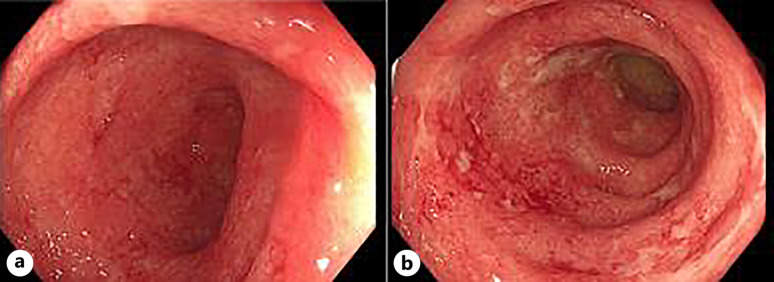

Introduction: Acute severe ulcerative colitis (ASUC) represents a medical emergency associated with high mortality and morbidity. While corticosteroids are the primary treatment, cases that are unresponsive often require rescue therapy with either infliximab or cyclosporine to reduce the rate of colectomy. Janus kinase inhibitors, such as tofacitinib and upadacitinib, are a highly efficacious therapy with rapid induction of clinical response in moderate to severe ulcerative colitis (UC). Limited data are available on its use on ASUC. We present the first case utilizing upadacitinib as sequential medical rescue therapy in ASUC as well as intestinal ultrasound as a useful tool for disease and response monitoring.

Case presentation: A 69-year-old female who presented with corticosteroid-refractory ASUC partially responded to dose-intensified infliximab and finally achieved clinical remission with upadacitinib. This resulted in swift clinical remission and significant improvement in her mucosal inflammation on intestinal ultrasound.

Conclusion: This successful intervention not only avoided colectomy but demonstrated sustained clinical and sonographic remission 16 weeks of post-treatment. Upadacitinib, with its rapid action and efficacy, shows promise in ASUC and should be supported by registration trials and real-world studies. Despite successful outcomes in this case, further validation and long-term data are necessary.